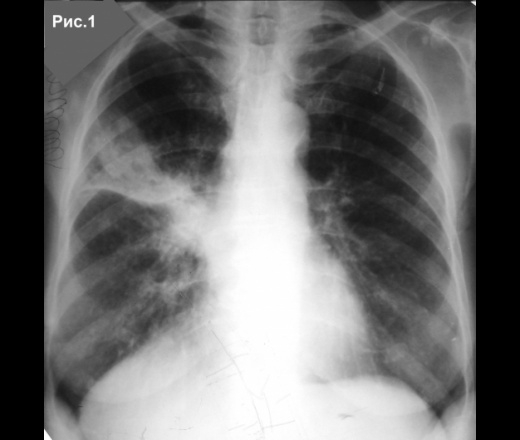

Воспалительный инфильтрат — описание болезни

Симптомы болезни Воспалительный инфильтрат

Воспалительные инфильтраты возникают как за счет контактного распространения инфекции (per continuitatum), так и лимфогенного пути при поражении лимфатического узла с дальнейшей инфильтрацией тканей. Инфильтрат обычно развивается в течение нескольких дней. Температура у больных бывает нормальной и субфебрильной. В области поражения возникают припухлость и уплотнение тканей с относительно четкими контурами и распространением на одну или несколько анатомических областей. Пальпация безболезненная или слабо болезненная.

Флюктуация не определяется. Кожные покровы в области очага поражения обычной окраски или слегка гиперемированы, несколько напряжены. Имеет место поражение всех мягких тканей данной области — кожи, слизистой оболочки, подкожно-жировой и мышечной ткани, нередко нескольких фасций с включением в инфильтрат лимфатических узлов. Именно поэтому мы отдаем предпочтение термину «воспалительный инфильтрат» перед термином «целлюлит», которым также обозначают подобные поражения. Инфильтрат может разрешаться в гнойные формы воспаления — абсцессы и флегмоны и в этих случаях его следует рассматривать как предстадию гнойного воспаления, которую не удалось купировать.

Диагностика болезни Воспалительный инфильтрат

Дифференциальную диагностику воспалительного инфильтрата проводят с учетом выявленного этиологического фактора и давности заболевания. Диагноз подтверждают нормальная или субфебрильная температура тела, относительно четкие контуры инфильтрата, отсутствие признаков гнойного расплавления тканей и резкой болезненности при пальпации. Другими, менее выраженными, отличительными признаками служат: отсутствие значительной интоксикации, умеренная гиперемия кожного покрова без выявления напряженной и лоснящейся кожи. Таким образом, воспалительный инфильтрат может характеризоваться преобладанием пролиферативной фазы воспаления мягких тканей челюстно-лицевой области. Это, с одной стороны, свидетельствует об изменени реактивности организма ребенка, с другой — служит проявлением естественного и терапевтического патоморфоза.